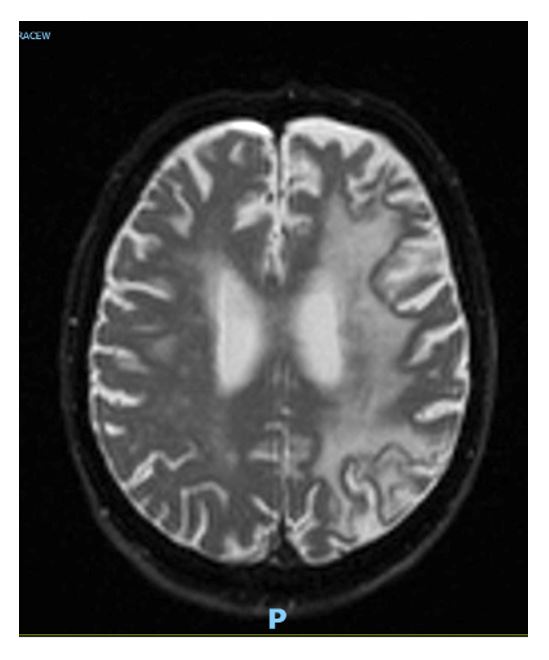

Figure 2: MRI – Auto-DIFF-TRACEW October 2024 at time of presentation demonstrating marked confluent L hemispheric white matter changes.